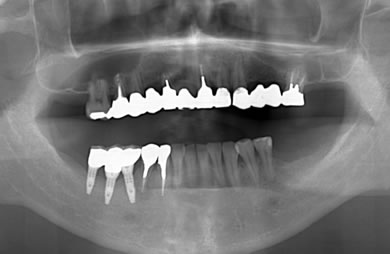

インプラントの症例写真 IMPLANT

スピードインプラント治療+セラミック治療

| 治療方針 | 欠損部位である右下6番とともに、隣接部位の破壊された歯周組織を回復。 | ||||||||||||||||||||||||||||||||

| 治療内容 | インプラント3本(抜歯即日スピードインプラント)、ハイブリッドセラミック3本 | ||||||||||||||||||||||||||||||||

| 総治療費 | 981.300円 | ||||||||||||||||||||||||||||||||

| 治療期間 | 8ヶ月 |